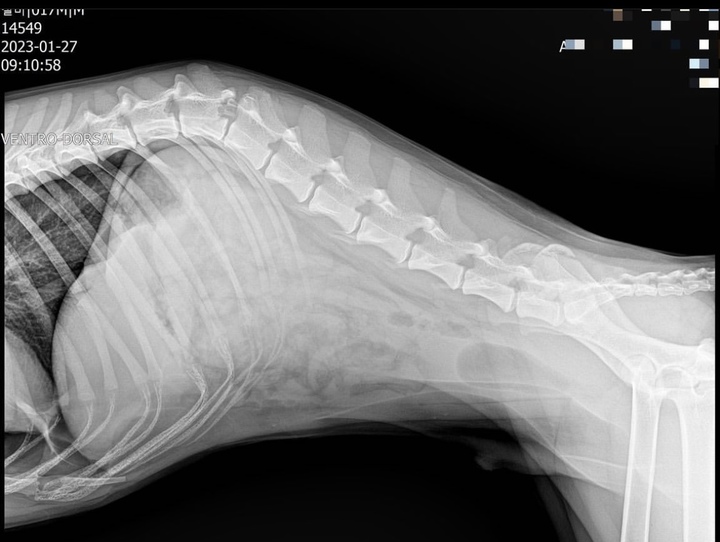

사고로 인해 뒷자리에 타고 있던 반려견은 척추가 부러져 긴급 수술을 받았으나, 뒷다리는 회복되지 않았다.

사진 인스타그램 'imzeolmi' 캡처 *재판매 및 DB 금지